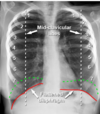

What would you see on a xray for someone with COPD

Hyperexpanded, enlarged lungs, air pockets (bullae) or a flattened diaphragm, and saber sheath trachea Barrel shaped chest